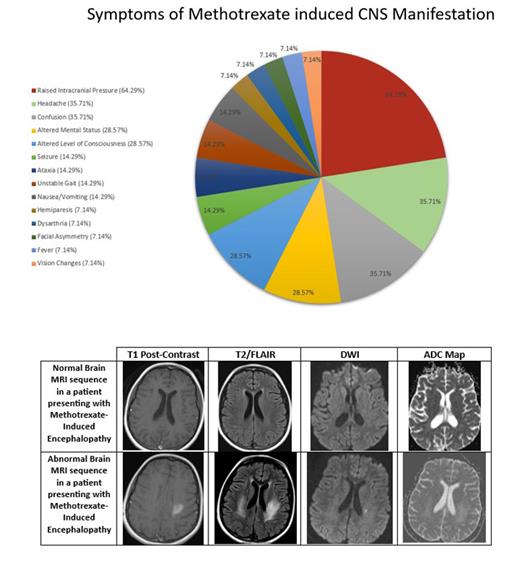

Sixty-five children were treated for ALL during the study decade. The average age at diagnosis was 4.7 ± 4 years. Our cohort consisted of 38 males and 27 females. Twelve of 65 patients (19%) developed MTX-induced CNS manifestations. The average age at the onset of symptoms was 5.3 ± 2 years. Ten patients had received a dose of IT MTX within 2 weeks of experiencing symptoms. Symptoms included raised intracranial pressure (ICP) (64%), headache (36%), confusion (36%), altered mental status (29%), and altered level of consciousness (29%).

Brain MRIs were obtained in all patients. Initial imaging studies yielded normal results in 6 (50%) patients. Abnormal findings included subcortical white matter changes, vividly observed on T2/FLAIR MRI. These changes were represented by regions of acute hyperintensity seen in diffuse bilateral cerebral hemispheres (33%), parietal regions (33%), frontoparietal regions (17%), occipital regions (17%) and the left parietooccipital region (17%). A follow up MRI was performed 3 to 8 months after the initial MRI and was repeated up to 6 times over a course of 6 years in a patient. The earliest MRI improvement was evident after 3 months of initial imaging.

About 20% of patients developed MTX induced CNS manifestations in our cohort. IT MTX was the most common culprit. Raised ICP, on opening pressure measured during IT procedures happened to be the most common finding. This has not widely been reported previously under MTX induced CNS complications in published data. One of the suspected etiologies is the inflammation of arachnoid villi impairing CSF drainage. These patients responded well to acetazolamide and therapeutic drainage of CSF. Finally subcortical while matter changes on T2/FLAIR MRI was a common CNS manifestation.